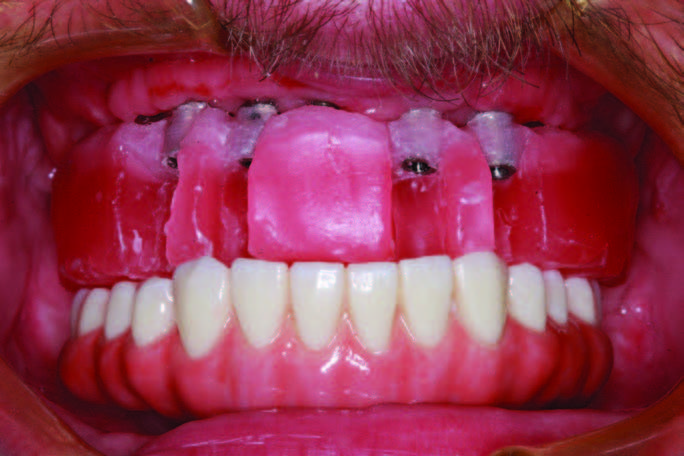

After implant placement and removal of the healing abutments, well-keratinized tissue was present that facilitated taking a good impression and cleanseability (Figure 12). After making the master impression, a baseplate and rim were ordered with instructions to engage every implant, leave windows for direct visualization at each implant site, and use metal componentry to aid as a secondary verification of seating (Figure 13). At this point, the Sheffield one-screw test was also performed to ensure the accuracy of the impression both with the baseplate and with the verification jig. When the custom abutments are designed and seated with abutment seating jigs, the verification jig is tried on; luted; and, if needed, separated and re-luted to ensure that there is no rocking or lifting with screw delivery (Figure 14). A custom tray was provided by the lab team, and it was tried in to learn the proper insertion path. Wax was then put in the screw access channel, and impression material (Aquasil Ultra Xtra) was injected around the abutments and used to load the tray. The impression was seated, and a finger was used to swipe away impression material to find the screw access channels. The working time of 5 minutes allows the dentist to relax while finding the screws. There is nothing more stressful than taking a full-arch implant impression and then losing your orientation and scrambling to seat it, as cutting off an impression intraorally can be a nightmare. This extended set and accurate impression material allows time for seating and the clearing of material (Figure 15). A full-arch impression is also made of the abutments after delivery to fine-tune gingival contours prior to fabrication of the monolithic BruxZir prosthesis (Glidewell Dental Laboratories).